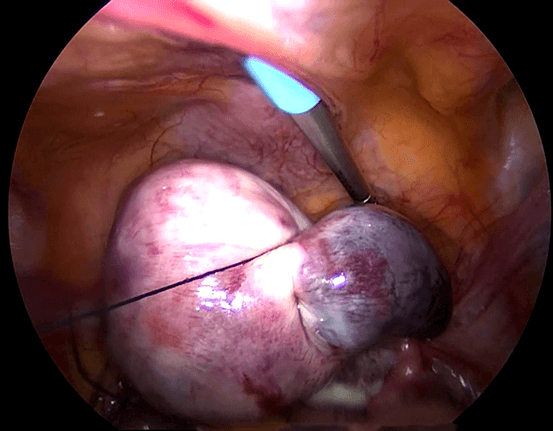

2) Salpingostomi Laparoskopi

Dalam teknik ini, sayatan dibuat di perbatasan antimesenterika (g) ( bagian dari tuba yang berlawanan dengan mesosalping (g) dari tuba falopi ), dan jaringan ektopik diekstraksi dari tuba. Sayatan pada tuba dapat dijahit atau mungkin tidak dapat dijahit. Apabila sayatan dijahit, operasi ini disebut dengan salpingostomi laparoskopi. Teknik salpingostomi laparoskopi biasanya dilakukan pada kehamilan tuba awal dan tidak pecah.

Keuntungan melakukan teknik ini adalah tuba masi utuh sehingga pasien dapat hamil dengan bantuan tuba ini di yang akan datang.

Kerugiannya adalah karena tuba mengalami bekas luka yang diakibatkan dari operasi, kehamilan ektopik lain dapat terjadi di tempat yang sama, dan juga resiko kecil bahwa setelah operasi beberapa kehamilan ektopik mungkin masih ada dan bisa berkembang di dalam tuba.

Dengan demikian, apabila teknik ini dilakukan, penting untuk melakukan pengulangan test darah ( serum beta HCG ) agar dapat memastikan bahwa tingkatnya telah menurun, sehingga mengindikasikan tidak adanya pertumbuhan yang lebih jauh dari kehamilan ektopik. Histerosalpingografi akan diperlukan setelah 3 bulan untuk memastikan apakah tuba masih paten. Teknik ini biasanya direkomendasikan apabila pasien hanya memiliki 1 tuba paten karena pengangkatan tuba akan memerlukan IVF bagi pasien untuk hamil.

Kehamilan spontan setelah Salpingostomi Laparoskopi untuk tuba kehamilan ektopik

NMA, merupakan seorang wanita yang berusia 33 tahun dan berkonsultasi kepada saya untuk pertama kalinya di tahu 2013. Dia sedang hamil 8 minggu. USG telah menunjukkan 2 kantong kehamilan yang terbentuk dengan baik tetapi tidak ada aktivitas pada janin. Dia menjalani kuretase hisap. Pasca operasi kondisi dia dalam keadaan yang baik dengan periode menstruasi yang teratur. Enam bulan kemudian dia mengalami nyeri panggul. Dia telah melewatkan menstruasinya dan test kehamilan menunjukkan hasil yang positif. USG menyatakan ukuran rahim normal tanpa kantong kehamilan intrauterin dan massa pada adneksa kiri dengan cairan di kantong Douglas. Diagnosis kehamilan ektopik telah dibuat.Dia menjalani salpingostomi laparoskopi ( simak video 26.2 ) . Pasca operasi kondisi dia baik-baik saja. Enam bulan kemudian dia menjalani histerosalpingogram ( HSG ) dan HSG menunjukkan tuba kanan paten , tuba kiri dapat dilihat tetapi tidak ada tumpahan perwarna. Dia menjalani inseminasi intrauterin sebanyak satu siklus namun itu dilakukan tanpa adanya keberhasilan. Dia hamil secara spontan dan empat bulan kemudian dan telah melahirkan bayi perempuan sehat pada tahun 2015.

Pembahasan

2 tipe operasi / pembedahan yang dapat dilakukan untuk kehamilan ektopik adalah (1) salpingostomi laparoskopi dan (2) salpingektomi laparoskopi. Salpingostomi laparoskopi hanya dapat dilakukan apabila tuba falopi tidak ruptur / pecah . Keunggulannya adalah pasien akan tetap memiliki tuba. Meskipun sakit, Dia mungkin bisa hamil secara spontan dengan tuba yang dioperasikan. Metode ini biasanya dipertimbangkan saat pasien hanya memiliki 1 tuba normal dan kehamilan ektopik terjadi di tuba itu. NMA ingin mempertahankan tubanya sehingga salpingostomi dilakukan. Dia akan menangung resiko kehamilan ektopik kedua yang berkembang di dalam tuba yang dioperasikan,namun beruntungnya dia hamil dengan kehamilan intrauterin dan telah melahirkan seorang anak.